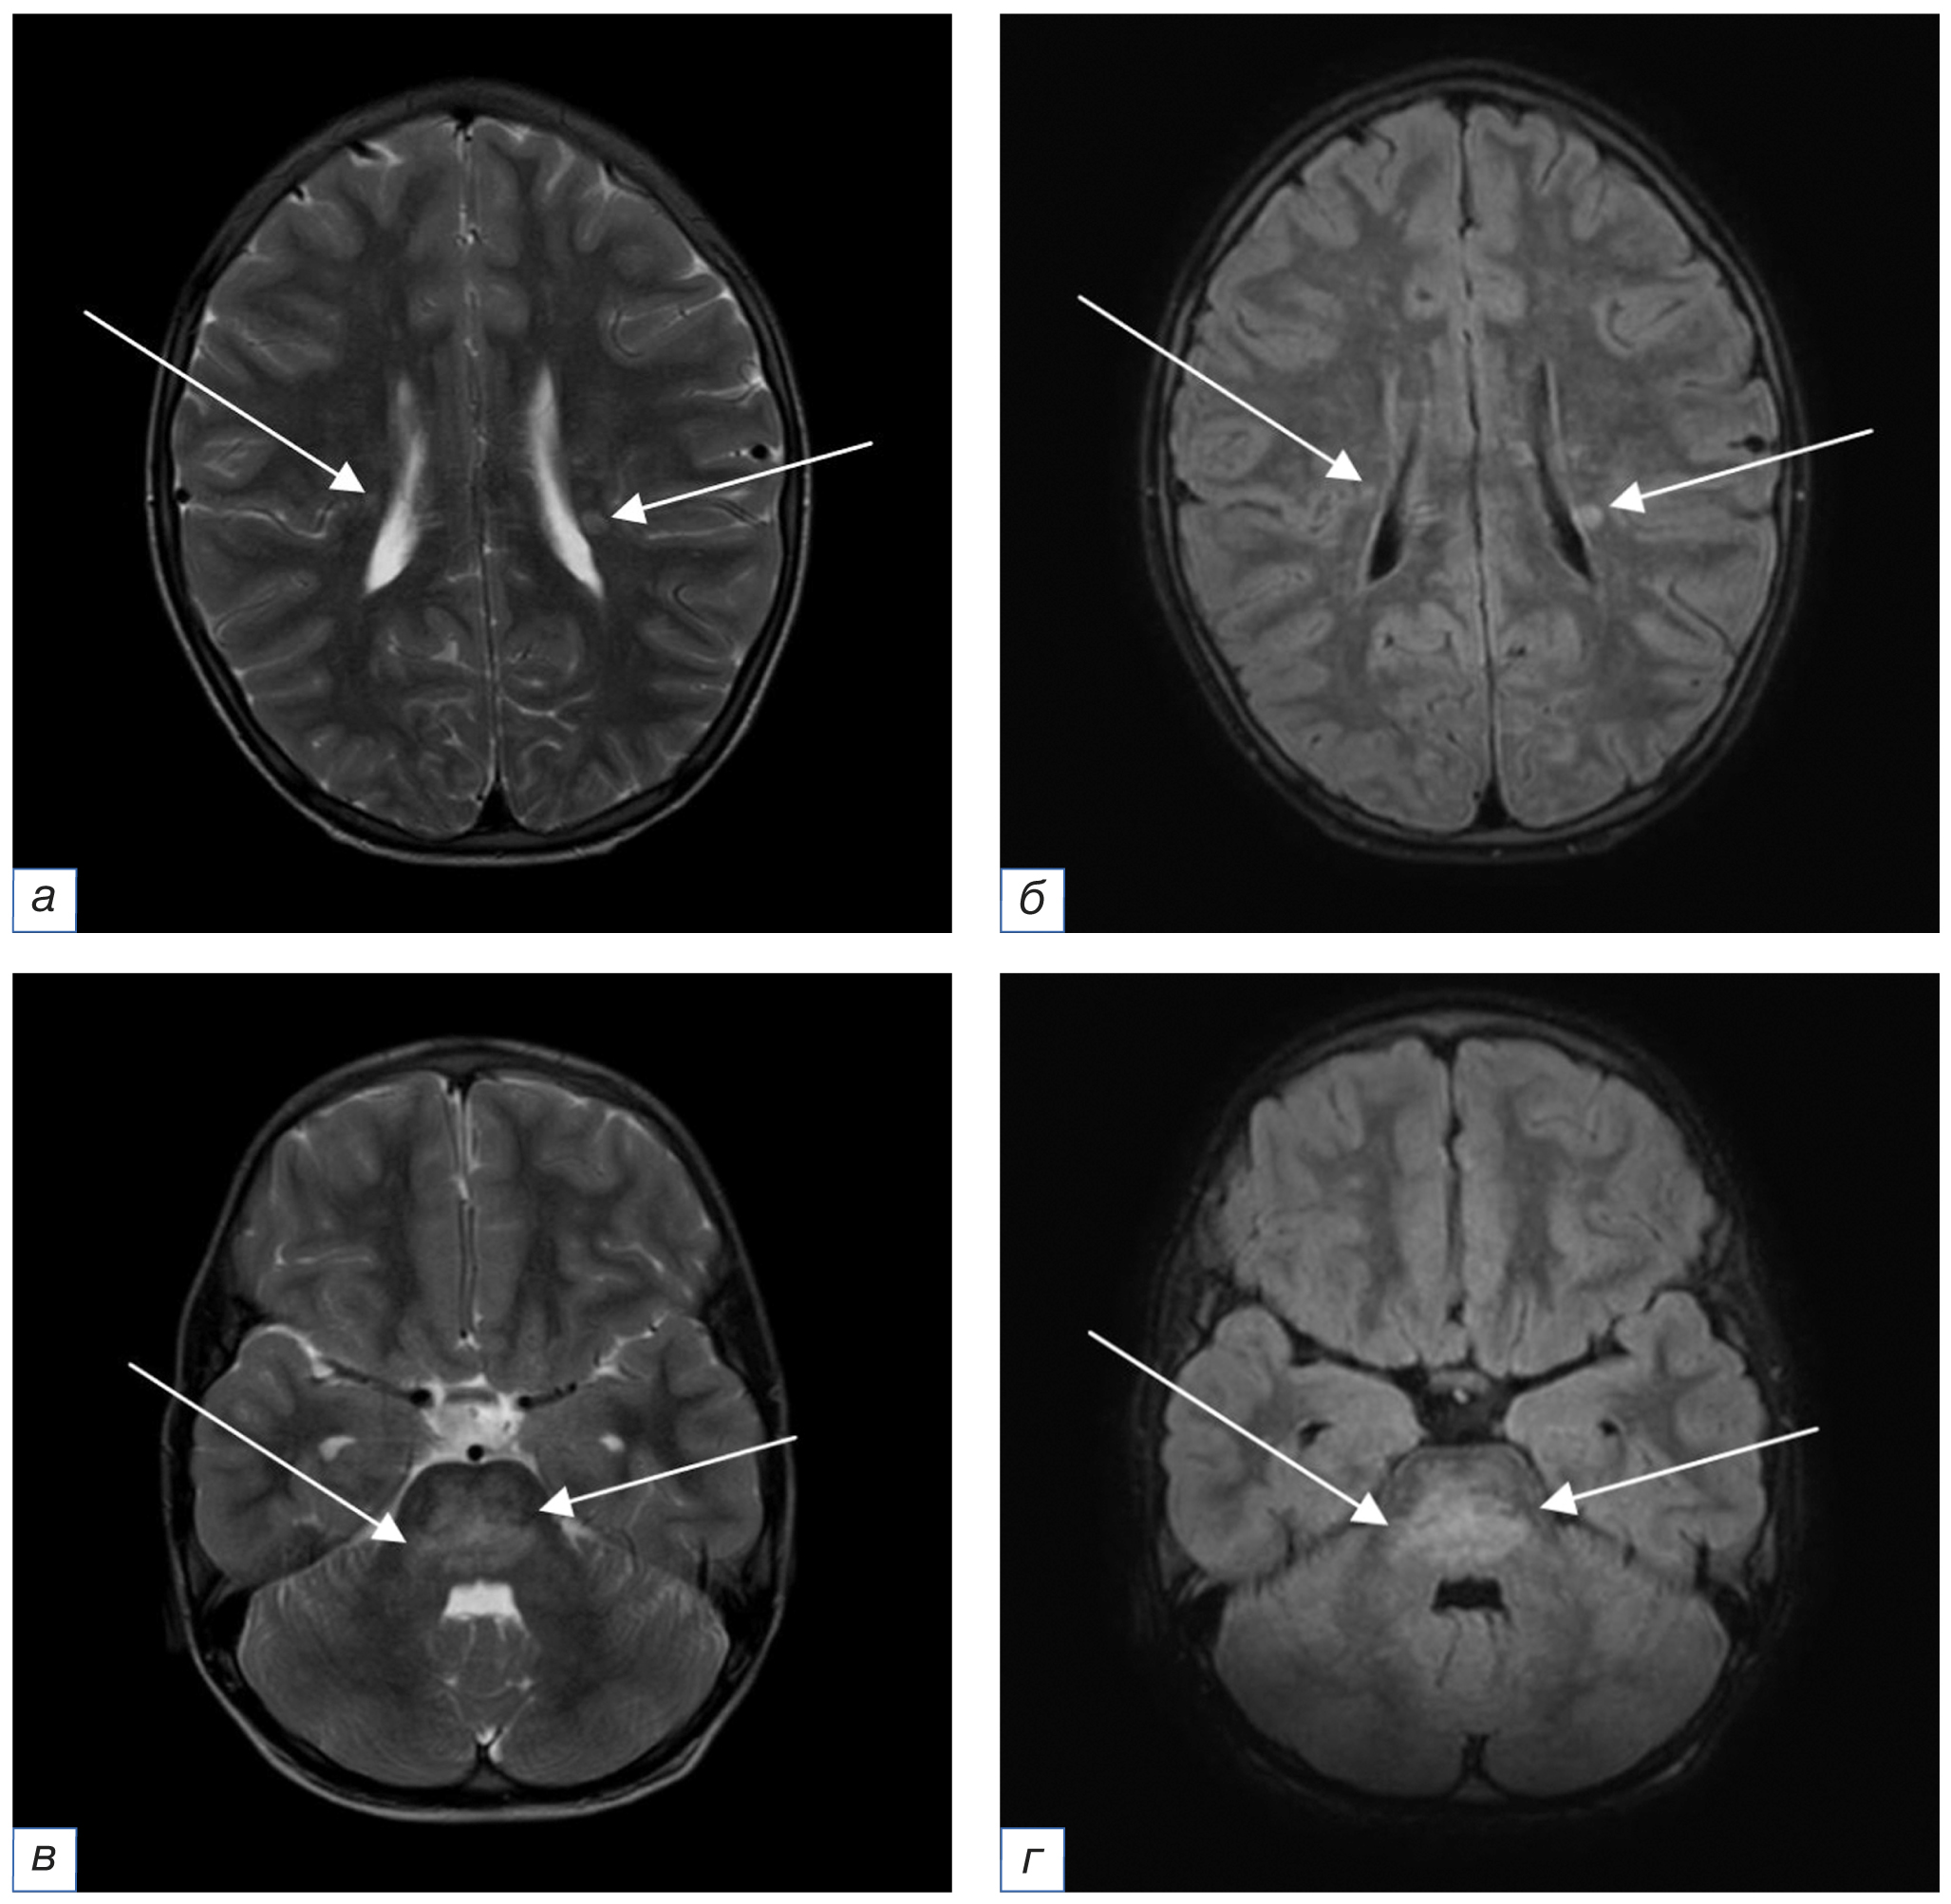

18.03.2022 (через 16 дней после пульс-терапии Метипредом) отмечалось ухудшение состояния ребенка в виде нарастания атаксии. МРТ головного мозга с контрастным усилением от 25.03.2022 (рис. 4) выявило отрицательную динамику: увеличение количества очагов измененного МР-сигнала. МРТ спинного мозга с контрастным усилением патологии не выявило. С целью исключения васкулита центральной нервной системы ребенку проведены МР-ангиография и церебральная ангиография: патологии не выявлено. Для купирования обострения основного заболевания проведена пульс-терапия метилпреднизолоном в дозе 750 мг внутривенно капельно. На фоне терапии отмечалась положительная динамика в виде уменьшения степени выраженности клинических проявлений. Далее с профилактической целью назначена терапия метилпреднизолоном в дозе 26 мг/сут перорально.

Рис. 4. МРТ головного мозга с внутривенным контрастным усилением в аксиальной плоскости от 25.03.2022 на фоне клинического обострения (a, в — режим Т2-ВИ; б, г — режим Т1-ВИ после введения контрастного вещества): по сравнению с данными МРТ от 16.08.2021 отмечается отрицательная динамика в виде увеличения размеров и количества очагов с интенсивным накоплением контрастного вещества (стрелки). / Fig. 4. MRI of the brain in the axial plane of March 25, 2022 with intravenous contrast enhancement in the acute stage of CLIPPERS (a, в — T2-weighted image; б, г — T1-weighted image after contrast enhancement): compared with the MRI data of August 16, 2021, a negative trend is observed namely an increase in the size and number of foci with strong contrast enhancement (arrows).

15.06.2022. По данным МРТ головного мозга с контрастным усилением (рис. 5) в сравнении с исследованием от 25.03.2022 отмечается положительная динамика в виде регресса ранее выявленных субтенториальных очагов.

Рис. 5. МРТ головного мозга с внутривенным контрастным усилением в аксиальной плоскости от 15.06.2022 после курса пульс-терапии и поддерживающей терапии кортикостероидами на протяжении 3 мес (a, в, д — режим Т2-ВИ; б, г, е — режим Т1-ВИ после введения контрастного вещества): по сравнению с данными МРТ от 25.03.2022 отмечается регресс очаговых изменений субтенториальных структур (стрелки). Участки патологического накопления контрастного вещества не определяются. / Fig. 5. MRI of the brain in the axial plane of June 15, 2022 with intravenous contrast enhancement after a course of pulse therapy and maintenance therapy with corticosteroids for three months (a, в, д — T2-weighted image; б, г, е — T1-weighted image after contrast enhancement): compared with the MRI data of March 25, 2022 there is a regression of focal changes in the subtentorial structures (arrows). Absence of pathological contrast enhancement.

27.10.2022. По результатам МРТ головного мозга с внутривенным контрастным усилением (рис. 6) на фоне поддерживающей терапии кортикостероидами на протяжении 7 мес не отмечается новых очаговых изменений, участков патологического накопления контрастного вещества не определяется. Однако выявляются сопутствующие вторичные изменения больших полушарий и моста, наиболее вероятно, соответствующие псевдоатрофии в результате уменьшения воспалительного отека на фоне стероидной терапии, с умеренным расширением ликворных пространств.

Рис. 6. МРТ головного мозга с внутривенным контрастным усилением в аксиальной плоскости от 27.10.2022 после поддерживающей терапии кортикостероидами на протяжении 7 мес (a, б — режим Т1-ВИ до и после введения контрастного вещества соответственно; в, д — режим Т2-ВИ; г, е — режим FLAIR): по сравнению с данными МРТ от 15.06.2022 появления новых очаговых изменений не отмечается. Участков патологического накопления контрастного вещества не определяется. Однако визуализируются изменения МР-сигнала в мосту (белые стрелки) и уменьшение объёма белого вещества больших полушарий с вторичным расширением ликворных пространств (красные стрелки), вероятно, как проявление псевдоатрофии на фоне стероидной терапии. / Fig. 6. MRI of the brain in the axial plane of October 27, 2022 with intravenous contrast enhancement after a maintenance therapy with corticosteroids for seven months (a, б — T1-weighted image before and after contrast enhancement respectively; в, д — T2-weighted image; г, е — FLAIR): compared with the MRI data of June 15, 2022 no new focal changes have appeared. Absence of pathological contrast enhancement. However there are changes of the MR signal in the pons (white arrows) and changes of the white matter of the brain hemispheres with secondary dilatation of liquor spaces (red arrows) specific to pseudoatrophy during the treatment with steroids.